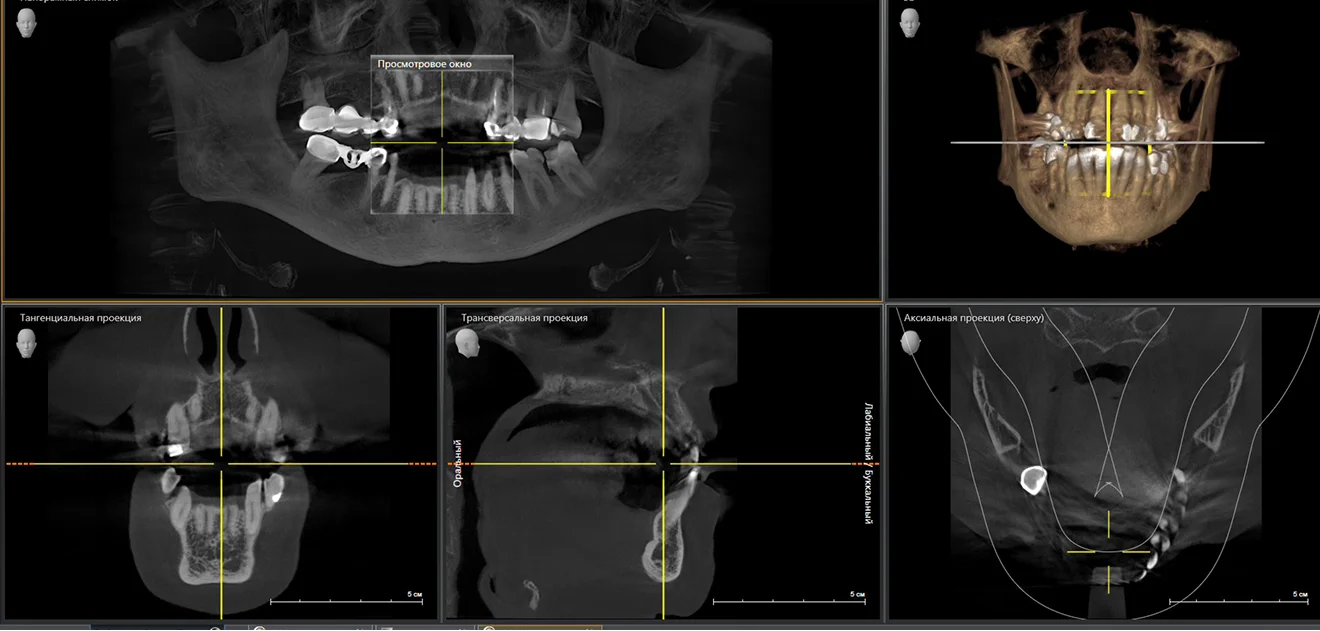

Спочатку — точна діагностика

Не починаємо лікування без аналізу КТ-обстеження щелеп та встановлення правильного діагнозу.

Цифрова діагностика та компʼютерне прогнозування результату

Цифрова діагностика

та компʼютерне прогнозування результату

Обстеження із застосуванням сучасного обладнання — для точного діагнозу та прогнозу подальшого лікування.

Наше кредо — встановлення ПРАВИЛЬНОГО діагнозу з допомогою цифрового обстеження та подальше лікування захворювань за протоколами світової доказової медицини

з допомогою цифрового обстеження та ефективне лікування захворювань за протоколами світової доказової медицини

Для надання професійної медичної допомоги в клініці застосовується сучасне обладнання та цифрові технології.